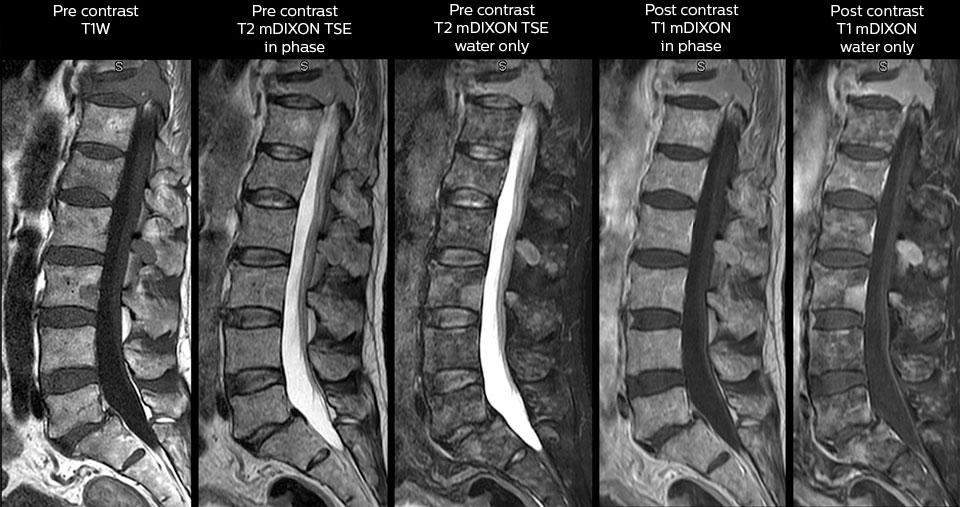

„Mit mDIXON TSE-Sequenzen ist es dank der T2-gewichteten Bilder auf Wasserbasis aus derselben Erfassung möglich, gleichzeitig morphologische Veränderungen aus den T2-gewichteten In-Phase-Bildern zu charakterisieren und ödematöse Veränderungen darzustellen. Auf diese Weise können anatomische und morphologische Befunde wie eine partielle oder komplette Bandruptur, ein knöcherner Ausriss oder ein Hämatom abgeklärt werden.“ „In Bezug auf die Beurteilung von Weichteilgewebe bietet mDIXON ähnliche Vorteile. Bei einer T2-gewichteten mDIXON TSE-Erfassung helfen die multiplen Kontraste zum Beispiel bei der Abklärung von pathologischen Befunden in Faserbündeln der peripheren Nerven, die auf anatomischen oder entzündlichen Veränderungen beruhen können.“ „Bei peripheren Gelenken erhalten wir mit mDIXON TSE eine gute Qualität in diffizilen Bereichen. Bilder mit Fettsuppression erscheinen vollständig homogen, auch bei einer großen Abdeckung mit 3,0 T – zum Beispiel beim Schulter- oder Beckengürtel – bzw. in den Gelenkflächen oder um Metallprothesen herum*, wo eine Fettsuppression mit STIR oder spektraler Suppression häufig unzureichend ist und zu Schwierigkeiten bei der Diagnose führt. Wenn ein diagnostisches Bild auf Anhieb richtig dargestellt wird, ist es nicht nötig, eine Sequenz zu wiederholen oder hinzuzufügen.“ „Mit mDIXON TSE-Sequenzen ist es dank der T2-gewichteten Bilder auf Wasserbasis aus derselben Erfassung möglich, gleichzeitig morphologische Veränderungen aus den T2-gewichteten In-Phase-Bildern zu charakterisieren und ödematöse Veränderungen darzustellen. Auf diese Weise können anatomische und morphologische Befunde wie eine partielle oder komplette Bandruptur, ein knöcherner Ausriss oder ein Hämatom abgeklärt werden.“ „In Bezug auf die Beurteilung von Weichteilgewebe bietet mDIXON ähnliche Vorteile. Bei einer T2-gewichteten mDIXON TSE-Erfassung helfen die multiplen Kontraste zum Beispiel bei der Abklärung von pathologischen Befunden in Faserbündeln der peripheren Nerven, die auf anatomischen oder entzündlichen Veränderungen beruhen können.“

„mDIXON TSE wird in unserer Notaufnahme ausgiebig für die Wirbelsäulenbildgebung eingesetzt“, führt Dr. Karis aus. „Besonders vorteilhaft ist, dass dieses Verfahren im Hinblick auf suszeptibilitätsbezogene Probleme sehr stabil ist, die häufig bei klassischen spektralen, fettgesättigten Bildern auftreten. Im Wesentlichen treten derartige Probleme beim mDIXON-Verfahren überhaupt nicht auf. Wir sind wirklich froh, in unserer Notaufnahme über die fettfreie Bildgebung des mDIXON-Verfahrens zu verfügen.“

„Für die routinemäßige, kontrastmittelfreie Untersuchung der Brust- und Halswirbelsäule führen wir zum Beispiel eine mDIXON T2-TSE-Sequenz durch, die uns zwei Ergebnisse liefert: die T2-gewichteten Bilder auf Fett- und Wasserbasis sowie die sagittalen T2-gewichteten Bilder auf reiner Wasserbasis. Anschließend erfolgt noch eine axiale Gradientenecho-Untersuchung.“